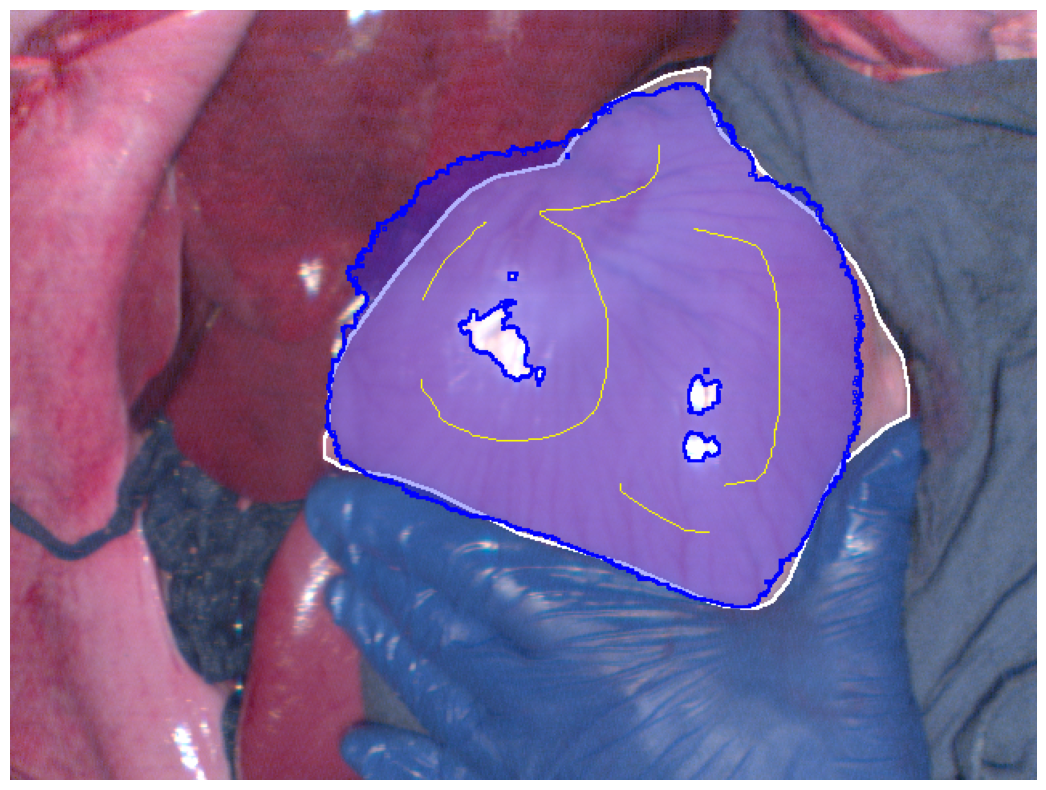

Refer to caption

(b) Hyperspectral image best Dice segmentation result

Figure 2: Segmentation results (blue regions) at the best Dice coefficient for different methods and ground truth (white regions), along with the curves of Dice coefficient variation with threshold adjustments.

In Fig. 2, the segmentation results at the best Dice for the four different methods are displayed, along with the variation in Dice coefficients with threshold adjustments. From Fig. 2e, it can be seen that the Euclidean distance method has the lowest maximum Dice score of 0.914. The methods using geodesic distance maps generated from hyperspectral images and reconstructed RGB images achieve similar maximum Dice values, both higher than the Euclidean method. The deep learning-based feature geodesic distance map method achieves the highest maximum dice coefficient.

For the 575 images in P086, automated scribbles were generated by skeletonizing the annotation results, and segmentation results were produced using pre-mentioned four different methods. Among these, the deep learning-based feature geodesic distance map method achieved the highest average max Dice score of 0.842, demonstrating its superior performance.